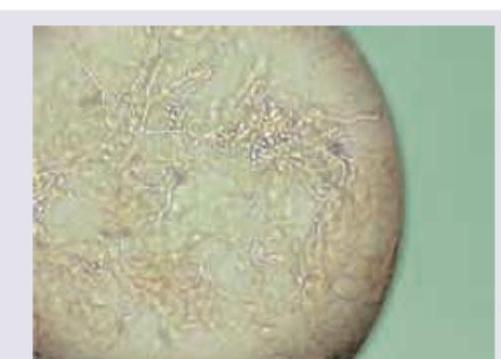

Explanation: ***Spaghetti and meatball appearance*** - This description refers to the characteristic microscopic appearance of *Malassezia* species on a **KOH mount**, showing short hyphae ("spaghetti") and spherical yeast cells ("meatballs"). - This finding is typical of **tinea versicolor** and sometimes seborrheic dermatitis. *Budding yeasts and pseudohyphae* - This appearance is characteristic of *Candida albicans*, which causes conditions like candidiasis or thrush. - While yeasts are present, the hyphae in the image are short and fragmented, unlike the continuous pseudohyphae of *Candida*. *Clusters of pigmented cells* - This description would be more indicative of conditions like **tinea nigra** or certain bacterial infections. - The image clearly shows fungal elements (yeasts and hyphae), not pigmented cellular clusters. *Septate hyphae* - While the image shows some hyphae, the dominant feature is a mix of short hyphae and round yeast forms, which is specific to *Malassezia*. - **Septate hyphae** alone are a general characteristic of many dermatophytes (e.g., *Tinea corporis*), but not the hallmark of *Malassezia* when combined with spherical yeasts.

Explanation: ***Pityriasis versicolor*** - The image clearly shows a KOH mount with **short, curved hyphae** and **clusters of round yeast cells**, characteristic of **spaghetti and meatballs** appearance, which is pathognomonic for *Malassezia furfur*, the causative agent of pityriasis versicolor. - This common superficial fungal infection presents as hypo- or hyperpigmented patches, primarily on the trunk, neck, and arms, and is diagnosed by this distinctive microscopic finding. *Tinea imbricata* - This is a rare form of tinea corporis caused by *Trichophyton concentricum*, characterized by **concentric, scaly rings**. - A KOH mount would show **long, branching hyphae** without the characteristic yeast clusters seen in the image. *Pompholyx* - **Pompholyx** (dyshidrotic eczema) is an endogenous eczematous condition characterized by **deep-seated vesicles** and bullae on the palms, soles, and sides of the fingers. - It is a non-infectious condition, and a KOH mount would show **no fungal elements**; instead, it would reveal inflammatory cells if any scraping were done. *Tinea capitis* - **Tinea capitis** is a dermatophyte infection of the scalp and hair, primarily affecting children. - A KOH mount from hair or scalp scrapings would show **arthrospores** (either endothrix or ectothrix) and **hyphae within or around the hair shaft**, not the yeast and short hyphae clusters characteristic of *Malassezia*.